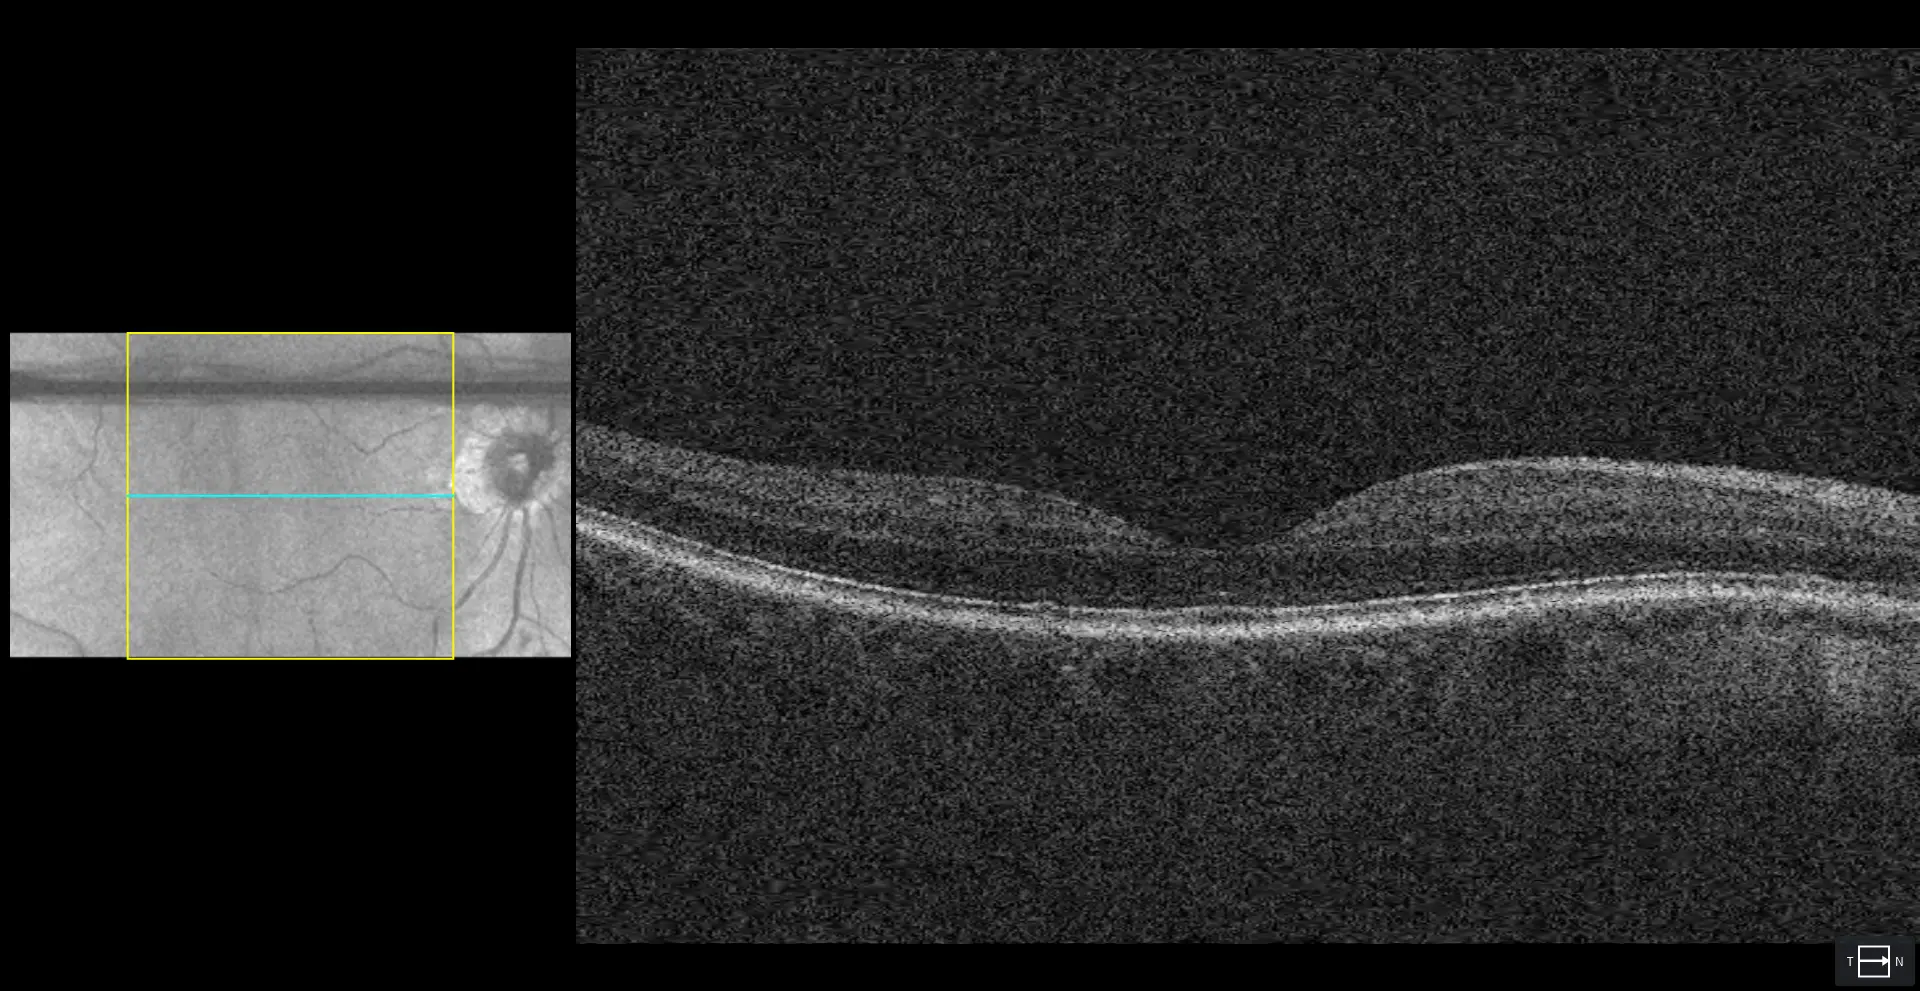

In-office testing showed low intraocular pressures in both eyes. Visual field testing of the right eye remained stable. The left eye showed a longstanding, dense superior defect consistent with previous macular and optic nerve changes from prior surgery, with no indication of progression. Ocular health was otherwise stable, and the patient was scheduled for routine monitoring with semiannual visual fields, OCT imaging, and pressure checks.

This patient has a complex ocular history, including prior macular hole repair in the left eye, LASIK in both eyes, and retinal surgery in the right eye. Current eye pressures are well controlled on topical therapy, with C/D ratios showing asymmetry (0.30 OD, 0.80 OS). OCT imaging shows some superior nerve thinning in the right eye, while visual fields remain normal.

Ongoing follow-up is recommended every 6–12 months, including OCT and visual field testing at each visit. Areas of note include asymmetry in optic nerve appearance and borderline OCT findings, while reassuring features include stable pressures and advanced age. The patient’s care continues collaboratively, with communication to their family physician and regular monitoring at the primary office.